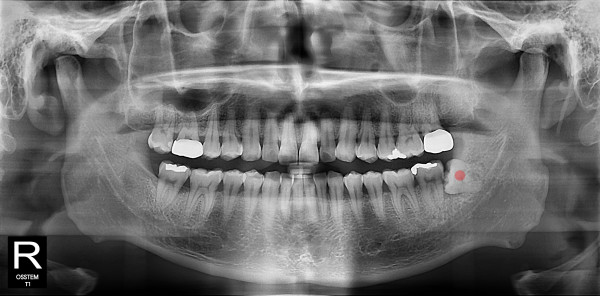

사랑니발치 20대/남성

ae27575af29d49719312fde5a1f0cca6_1764402576_9324.jpg